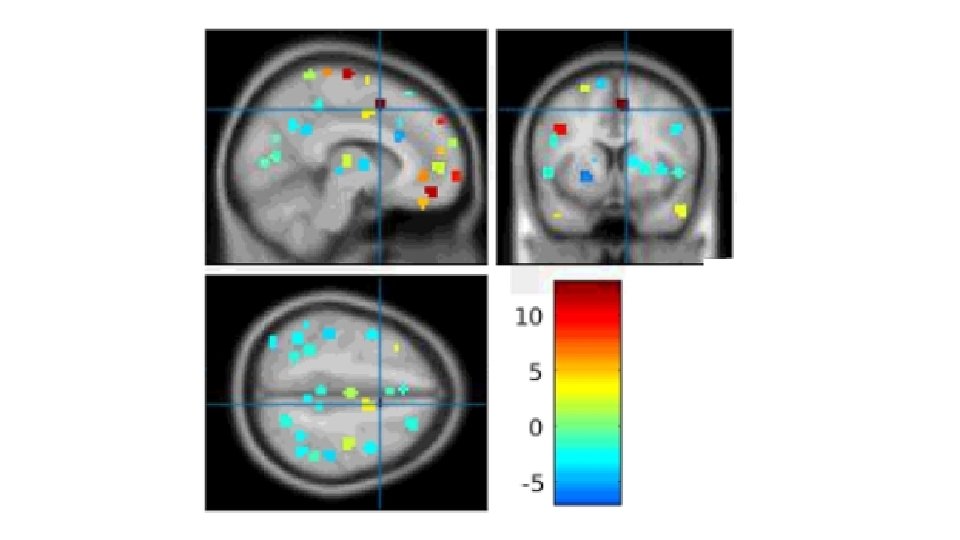

Resultados de contrastes Despertar tipo 1 (rojo) vs Despertar tipo 2 (celeste) - p < 0. 001 Activación bilateral con un máximo global en la corteza de la Unión Temporoparietal derecha (TPJ). Coordenadas MNI: x = 51; y = -70; z = 8.